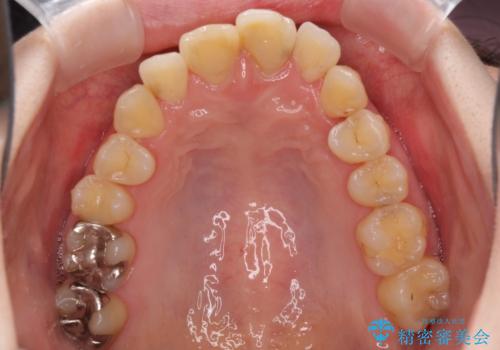

上下前歯のデコボコをきれいに インビザラインによる矯正治療

- 前歯の著しい叢生と前突感を気にして来院された患者様です。

叢生が強いため、事前に前歯をワイヤー矯正で速やかに叢生を解消し、その後はインビザラインにて矯正治療を行うこととしました。

ワイヤー矯正を併用したことで前歯の叢生を速やかに解消することができました。

一方口元の突出感を改善するために時間がかかり、2年超を要しましたが、満足のいく仕上がりとなりました。